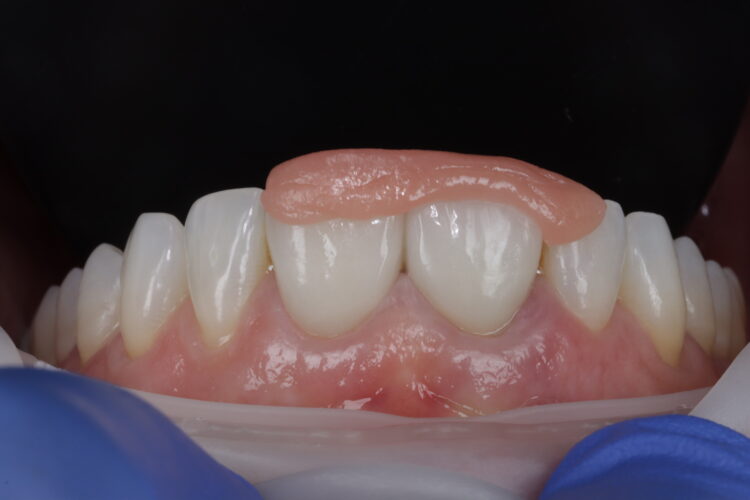

The implant was placed in close contact with the palatal bone, 1mm below the buccal bone height. A temporary cylinder abutment was connected, with flowable composite placed to attach the temporary restoration. The composite resin was used to create the optimal emergence profile ensuring a highly polished restoration in the transition zone.

Soft tissue regeneration

A free gingival graft was harvested from the palate, allowing enough tissue to reach between the base of each papilla and this was de-epithelialised to obtain the connective tissue. A thickness of 1mm is adequate, but in this instance, it was made intentionally thicker at the disto-buccal aspect to help plump up the papilla where bone loss was greater. The connective graft tissue was stabilised with three resorbable sutures placed, positioning the connective tissue graft 1mm below the free gingival margin.

The temporary restoration was then reintroduced and the surgical site closed tension-free. Vertical sling sutures were placed through both papillary areas over the contact points to hold the tissue up, create a prosthetic sealand to combat natural shrinkage.